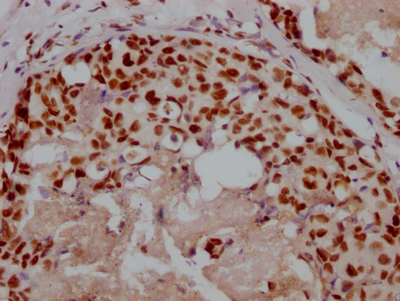

應用范圍:ELISA, IHC

Application Recommended Dilution IHC 1:20-1:200 -